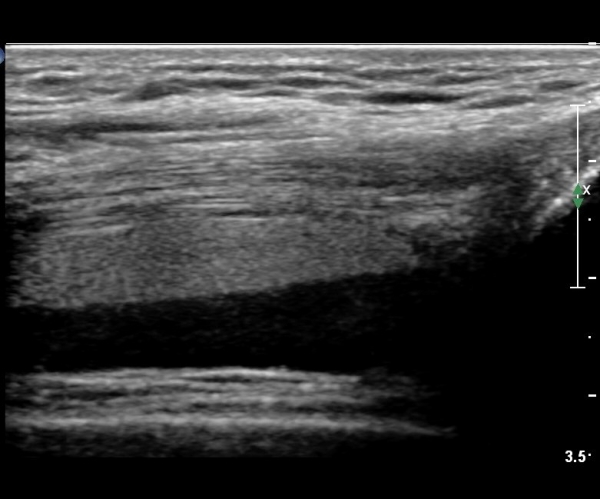

ÃÊÀ½ÆÄ °Ë»ç

¹«¸­ ÃøºÎ Á¾´Ü¸é°Ë»ç¿¡¼­ °í¿¡ÄÚ ¼ö¾×Àý·ù°¡ °üÂûµÊ( »çÁø 1).